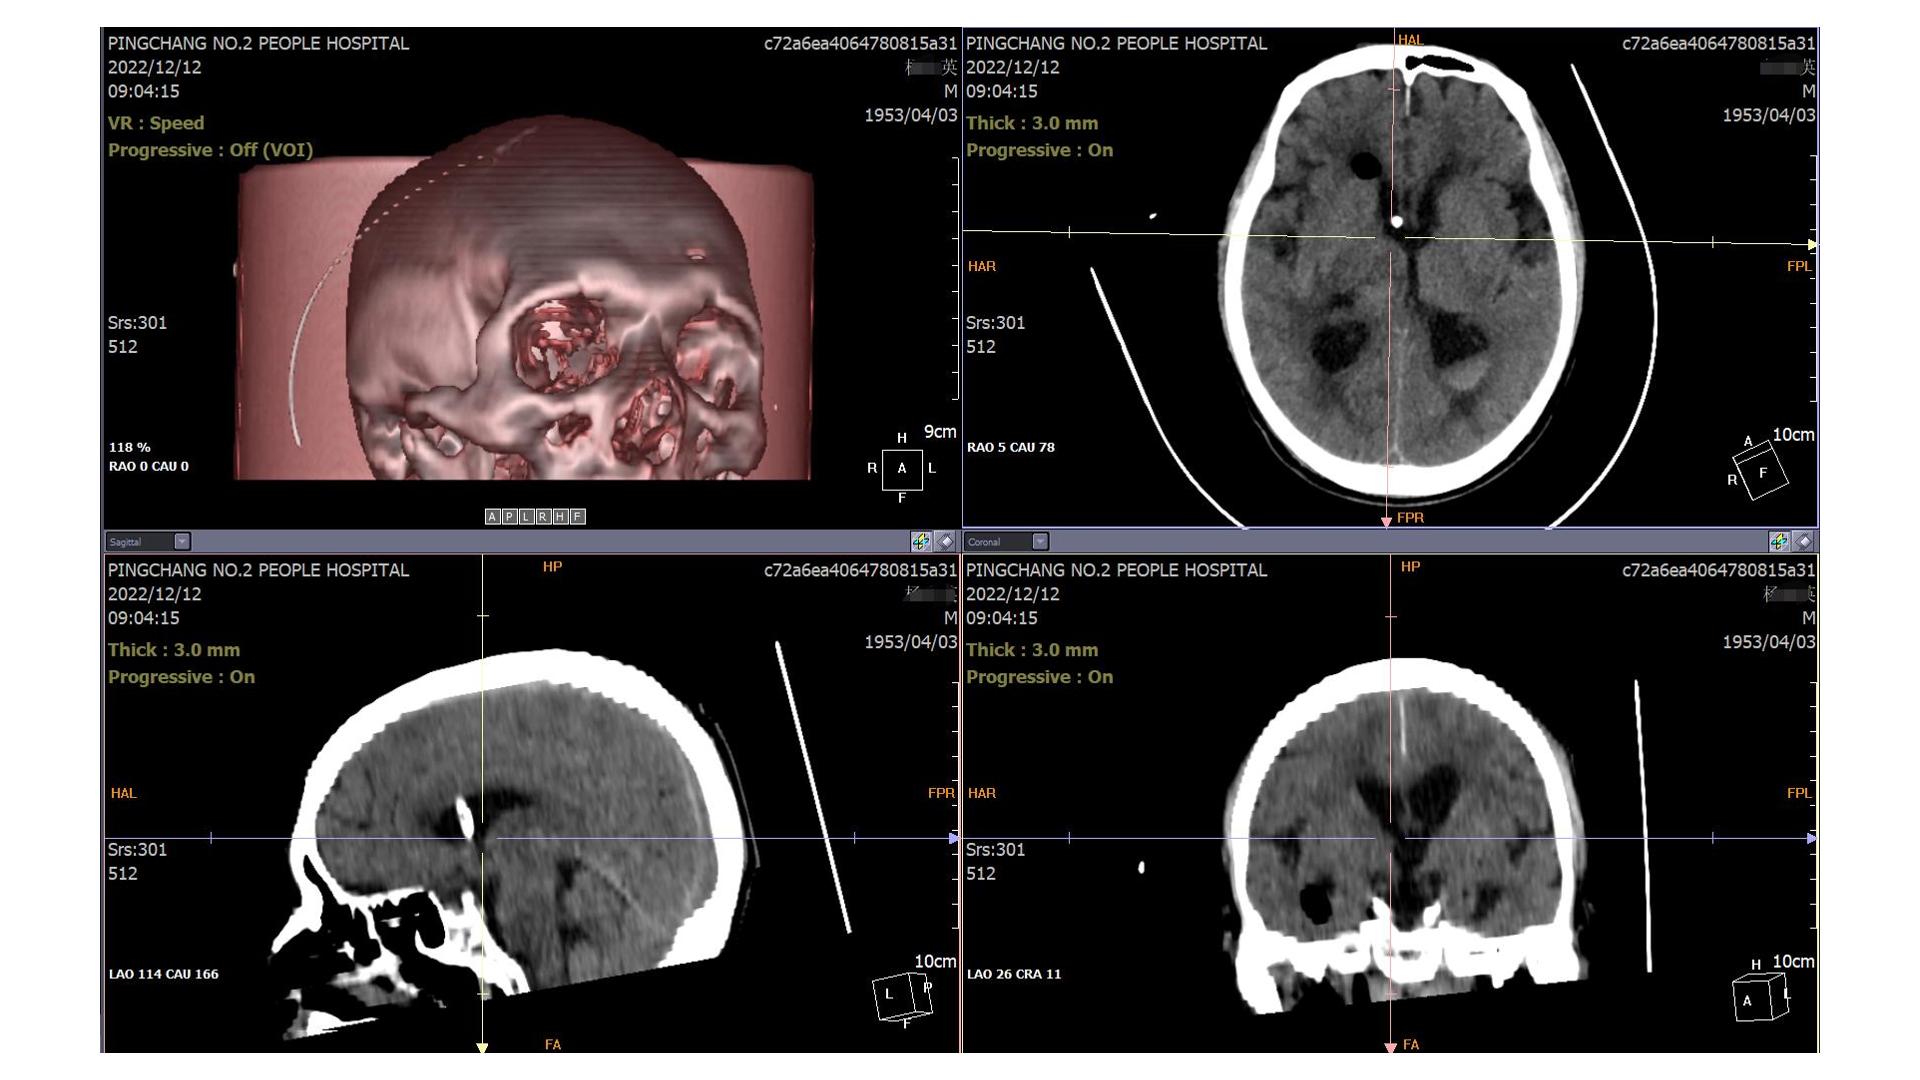

2022.12.12

2022.12.12,血肿基本干净,留取脑脊液送检无颅内感染征象,予以拔除EVD引流管,腰穿释放蛛网膜下腔血性脑脊液